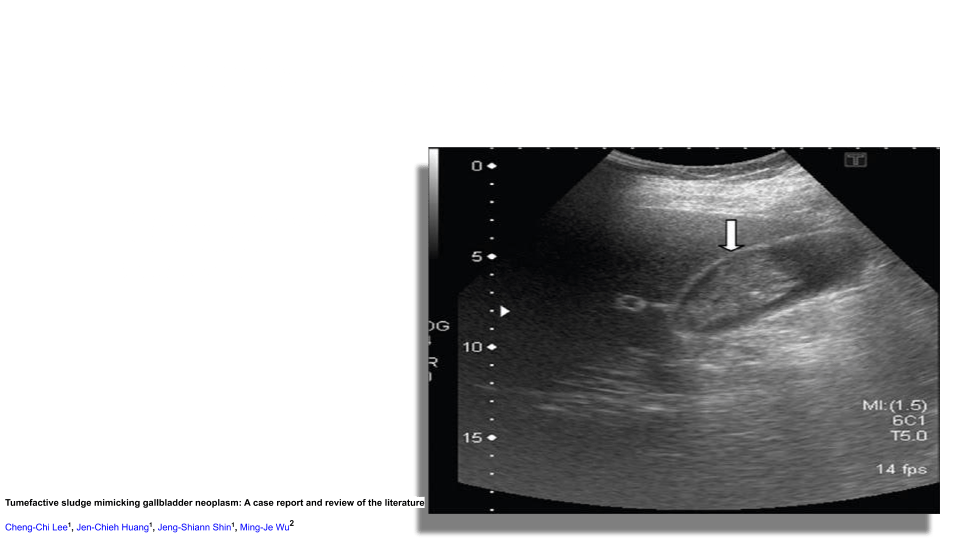

On ultrasound you’ll see low level echoes to echogenic debris that layers in the dependant part of the GB and is mobile with patient position. Sludge may aggregate into clumps which may simulate masses or polyps. This is known as tumefactive sludge. The gallbladder may also be completely filled with sludge making the whole GB complex isoechoic to the liver known as hepatization.

- Fakhry, J. “Sonography of Tumefactive Biliary Sludge.” American Journal of Roentgenology, vol. 139, no. 4, Oct. 1982, pp. 717–719, 10.2214/ajr.139.4.717.